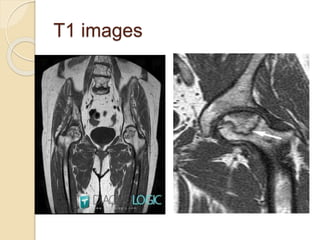

T1 images

T2 images

MRI features of osteonecrosis

 T1W characteristic serpiginous area of altered signal

intensity of anterosuperior part of femoral head.

 T2WI double line sign(pathognomonic)

Outer low intensity rim and inner high intensity

band

bright band sign